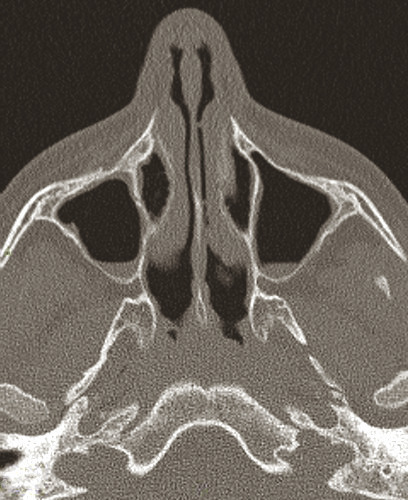

En l’absence d’endoscopie nasale, le praticien peut s’appuyer sur la tomodensitométrie qui montre une opacité plus ou moins complète des sinus. Mais cette image ne doit pas être interprétée sans interrogatoire et examen clinique car beaucoup d’enfants, surtout en période froide, ont ces anomalies sans avoir aucun symptôme de rhinosinusite chronique. L’imagerie a aussi un intérêt pour rechercher un facteur anatomique favorisant la rhinosinusite chronique tel qu’une déviation majeure de la cloison nasale, une cellule de Haller, une concha bullosa (fig. 4 ),5 ou une tumeur endonasale.

En l’absence d’endoscopie nasale, le praticien peut s’appuyer sur la tomodensitométrie qui montre une opacité plus ou moins complète des sinus. Mais cette image ne doit pas être interprétée sans interrogatoire et examen clinique car beaucoup d’enfants, surtout en période froide, ont ces anomalies sans avoir aucun symptôme de rhinosinusite chronique. L’imagerie a aussi un intérêt pour rechercher un facteur anatomique favorisant la rhinosinusite chronique tel qu’une déviation majeure de la cloison nasale, une cellule de Haller, une concha bullosa (